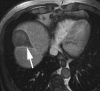

Transcatheter intraarterial therapies have proved valuable in the battle against primary and secondary hepatic malignancies. The unique aspects of all such therapies are their reduced toxicity profiles and highly effective tumor responses. These unique characteristics coupled with their minimally invasive nature provide an attractive therapeutic option in patients who may have previously had few alternatives. The concept of all catheter-based intraarterial therapies is to selectively deliver anticancer treatment to tumor(s). These therapies, which include transarterial embolization, intraarterial chemoinfusion, transarterial chemoembolization with or without drug-eluting beads, and radioembolization with use of yttrium 90, inflict lethal insult to tumors while preserving normal hepatic parenchyma. This is possible because hepatic neoplasms preferentially derive their blood supply from an arterial source while the majority of noncancerous liver is supplied by the portal vein. As part of the interventional oncology review series, in this article we describe the rationale behind each of these transcatheter therapies and provide a review of the existing medical literature.